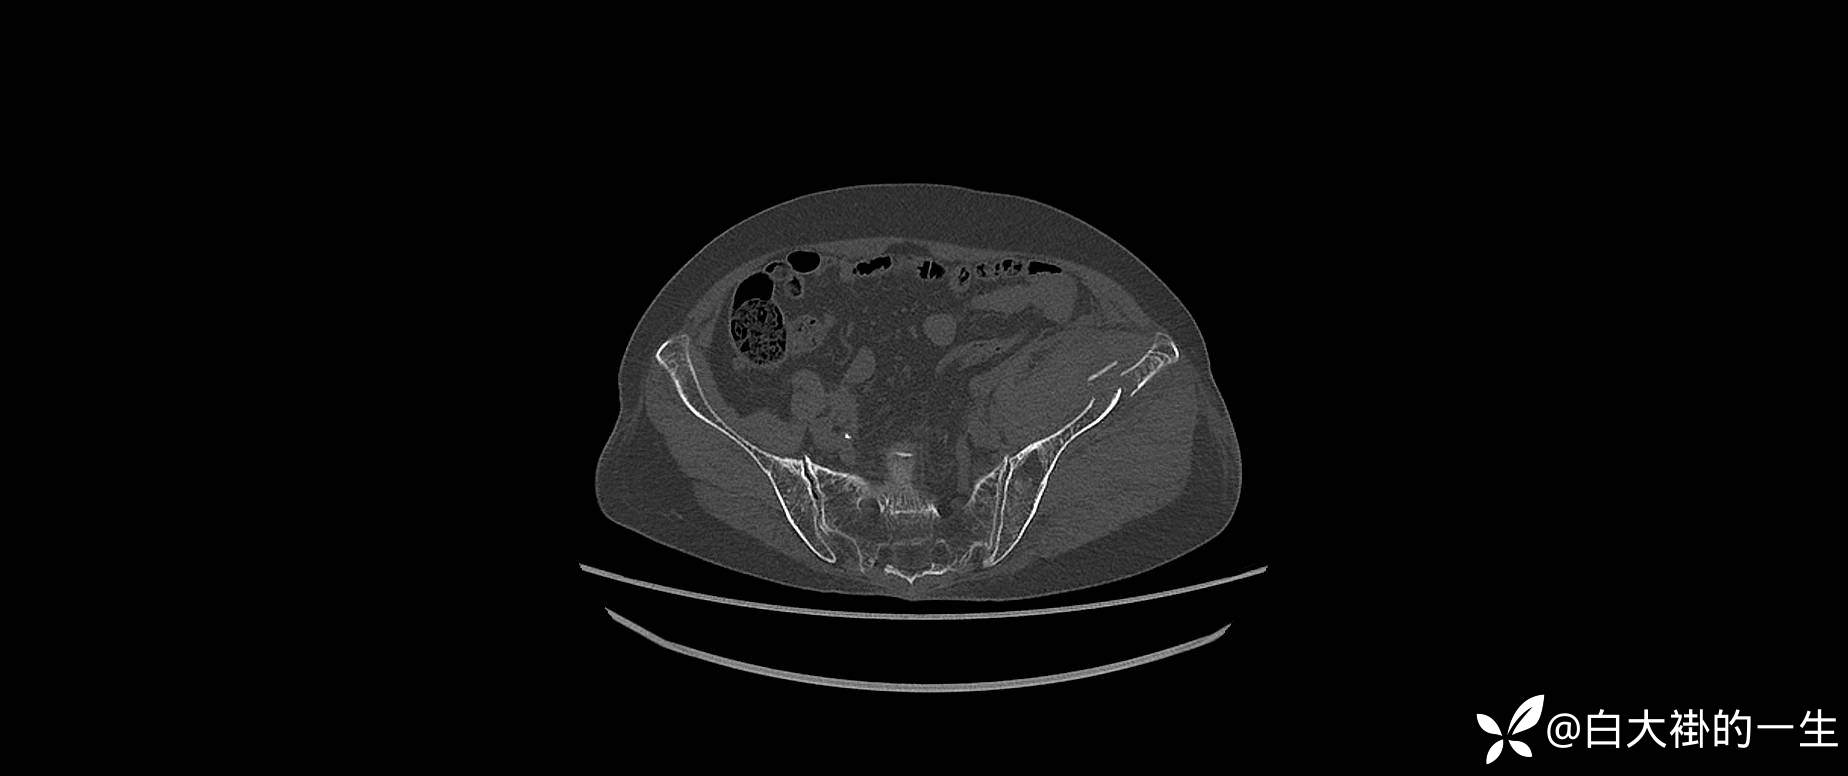

2024-08-03外院DR:左髂骨粉碎性骨折。

入院诊断:1.左髂骨粉碎性骨折;2.左髋部皮肤擦伤。

影像学如图: